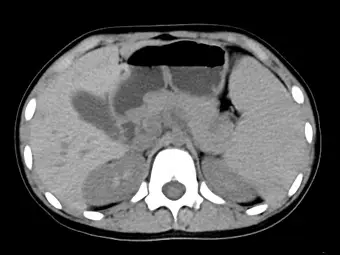

患有遺傳性球形紅血球增多症( hereditary spherocytosis )之女童,因貧血長期接受輸血治療。未施打顯影劑的腹部電腦斷層顯示肝脾腫大(如下圖所示),經測量其肝臟密度約為 75 HU ,顯示肝臟內可能堆積下列何種成分?

- 檢查造影:無對比劑(未施打顯影劑)腹部電腦斷層(Unenhanced abdominal CT)。

- 肝臟發現:影像中肝臟實質(Liver parenchyma)呈現均勻的高密度 (Hyperdense)。正常未施打顯影劑的肝臟密度約落在 40~65 HU,而本題測量出肝臟密度達 75 HU。因為肝臟實質密度異常升高,使得肝內未強化的血管(如肝靜脈、門靜脈)在明亮的肝臟背景下,呈現出非常明顯的相對低密度(暗色)分支管狀結構,此為典型的「白肝 (White liver)」表徵。

- 脾臟發現:影像顯示嚴重的脾臟腫大(Splenomegaly),脾臟體積龐大並向內下方延伸。這與患者本身患有遺傳性球形紅血球增多症(異常紅血球在脾臟被大量破壞引起慢性血管外溶血)的臨床病史完全吻合。